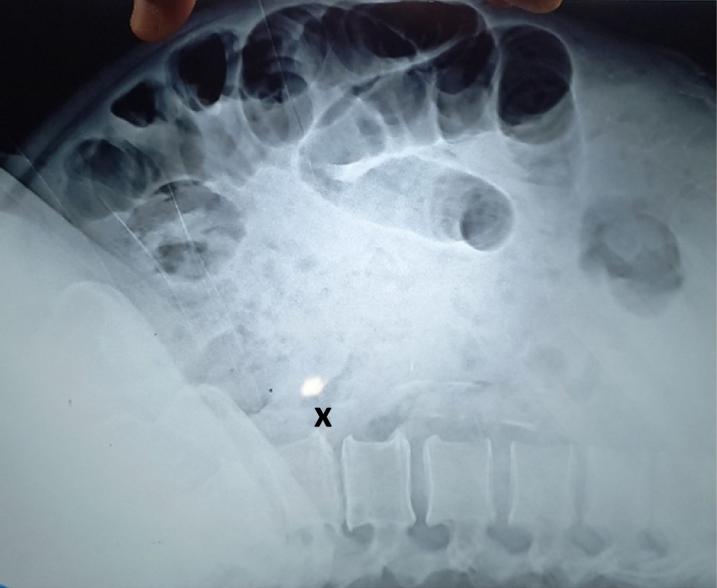

Suspecting he was going into septic shock, medics rushed the man to intensive care, where scans revealed that his abdomen was filling with fluid. This symptom suggested that his kidneys had stopped working — a possible sign of sepsis, where the body’s immune system attacks its own organs.

A subsequent two-hour operation revealed a small hole in his intestine, which the medical staff discovered was caused by an 0.8-inch-long fishbone. However, the farmer didn’t recall ingesting the 2-centimeter shard, the Daily Mail reported.

Nonetheless, the seemingly innocuous bone fragment had reportedly perforated his bowel, causing fecal matter to seep out and infect his abdominal wall. As a result, the intestine ballooned in size while yellow pus accumulated around the hole.